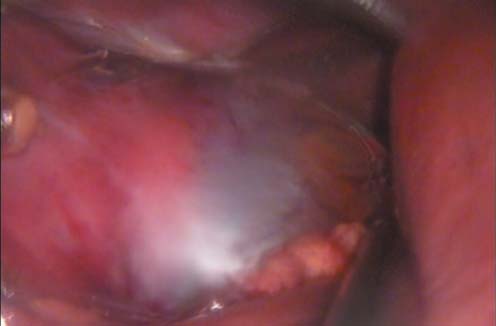

Операция проводилась с помощью стандартного набора инструментов для лапароскопии. При ревизии органов брюшной полости патологии не выявлено. Далее произведена мобилизация восходящего отдела толстой кишки, для этого произведен разрез брюшины по линии Тольда. Кишка смещена в медиальном направлении. Хорошая мобилизация кишки нам представляется особенно важным моментом для адекватного доступа к забрюшинному пространству. Особенно это актуально при операциях по методике единого доступа, где не предполагается введение дополнительного инструмента для отведения кишки. После обнажения забрюшинного пространства выделен верхний сегмент почки с кистой (рис. 3).

Рис. 3. Выделенная киста почки